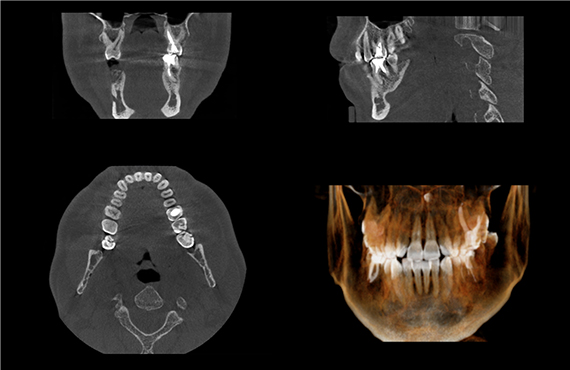

CT撮影

3Dデジタルで歯の内部や顎の骨の状態など様々な角度から検証し、症状を診断します。